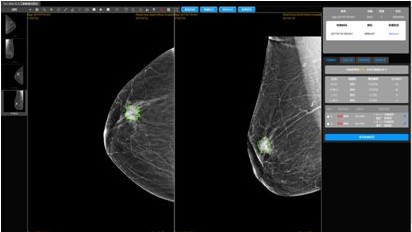

(华建蓝海莲花医生B端界面图)

谈及人工智能一个离不开的话题就是临床应用,来自福建医科大学附属协和医院薛蕴菁教授,山东省千佛山医院的李爱银教授分享了和华建蓝海成立“人工智能联合实验室”后,经过近一年的不断努力,在跨区域乳腺钼靶影像的自适应人工智能的诊断方法上取得了国际领先的成果,人工智能判读技术算法在跨区域乳腺钼靶影像数据集得到了目前世界上最好的AUC分数之一 0.9413,每个病例的CAD判读时间为0.3秒。

莲花医生是华建蓝海专为女性打造的基于人工智能全诊疗周期乳腺健康管理平台,涵盖筛查、诊断、治疗、回访全流程。目前在乳腺钼靶诊断领域已与国内顶级三甲医院达成合作。

华建蓝海莲花医生打造的全诊疗周期乳腺健康管理平台,不只提供AI智能辅助判读,还提供开放集成、深度学习、个性化定制、健康档案等全程服务,涵盖乳腺健康管理全诊疗周期,用人工智能技术,赋能女性健康。